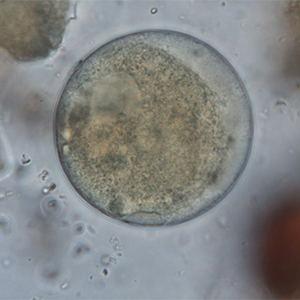

Le kyste est sphérique à ovoïde, à paroi épaisse, mesurant 50 à 100 μm de diamètre. Il présente un contenu granuleux, un macronucléus et micronucléus difficilement visibles (Strait et al., 2012). La coloration au Lugol permet de mettre en évidence certains organites qui apparaissent en brun sombre, de colorer la paroi en brun et l’intérieur du kyste en jaune.